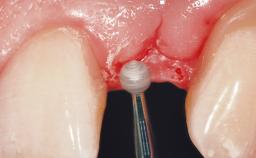

Late Flapless Placement of an Implant in a Maxillary Left Central Incisor Site

A 39-year-old male patient presented with a chief complaint of discomfort and gingival discoloration around his maxillary left central incisor. He was in good general health and was a non-smoker. His past dental history was significant because of the traumatic fracture of tooth 21 in a sporting accident at age 13. Initial dental treatment included endodontic therapy and a full-coverage restoration. The patient became symptomatic 5 years later, when structural failure of the tooth resulted in the dislodgment of the crown. Endodontic retreatment, apical surgery, and post-and-core restoration were performed.

Bone Volume Deficient horizontally, requiring prior grafting